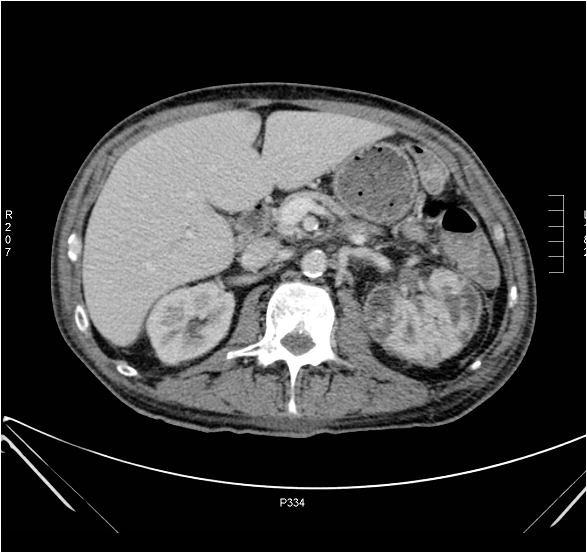

Currently, CT is the preferred imaging method in acute pyelonephritis. However, the radiologic picture often does not fully correlate with the clinical symptoms.

Intravenous pyelogram and US examinations may give negative results in over two third of the cases.

On the multiphase CT scan the affected parenchymal segment shows delayed contrast enhancement compared to its surroundings, and in the excretory phase it demonstrates a hypodense striated structure.

When abscess formation is suspected a CT scan must be performed. On the CT solitary or multiplex, circumscribed, round defects with a contrast enhancing wall are seen. Corresponding to the secondary perinephric stranding and to the extensive inflammation, abscesses can extend into the perinephric space. In such cases, depending on the severity of clinical symptoms, CT or US guided puncture can be attempted as a therapeutic intervention.

Image

Figure 7. CT image of extensive pyelonephritis involving the left kidney.